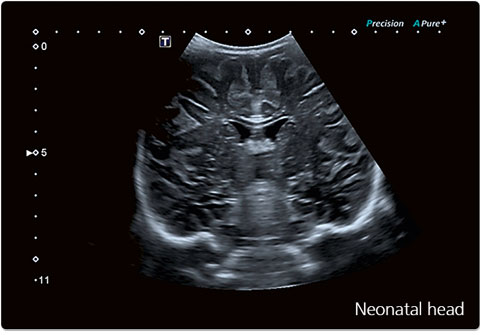

Échographe haute résolution Canon Aplio

Système d’échographie de dernière génération offrant une excellente qualité d’image, une analyse précise des organes et un confort optimal pour le patient.

L’échographie est un examen d’imagerie médicale non irradiant utilisant les ultrasons pour explorer les organes, les tissus mous et les structures internes en temps réel.